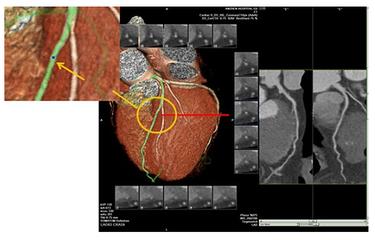

3.冠動脈CT検査:

64列CTの誕生と動的追跡技術の開発により、非侵襲的な方法で心臓の血管を検査し、冠動脈の狭窄の有無と程度を特定することができるようになった。この技術は、針や手術室を怖がる胸部圧迫感や胸痛のある多くの患者に役立っている。この検査の主な原理は、造影剤を静脈内に注射し、造影剤で満たされた冠動脈をCTでらせん状にスキャンすることです。 その後、冠動脈の各スキャンスライスを画像結合技術で結合して冠動脈の画像を形成します。

この検査は非侵襲的で安全ですが、いくつかの欠点があります、①リズムコントロール64列CTは心拍数を60拍/分以下にコントロールする必要があり、より速い128列とデュアルソースCTも心拍数を70拍/分以下に可能な限りコントロールする必要があります。この文章を覚えて、もし冠状動脈CT検査で冠状動脈性心臓病ではないと言われたら、この文章の信憑性は99%に高いが、もし冠状動脈CT検査で冠状動脈性心臓病と言われたら、この文章の信憑性は70%しかない。

5.冠動脈CTA(CT冠動脈造影)ヨード造影剤を血管内に注入する方法である。血管内にヨード造影剤を注入し、CT(コンピュータ断層撮影)で冠動脈を見て、奇形や心筋のブリッジ、冠動脈のプラークや狭窄の有無を確認するものです。この方法の利点は「非侵襲的」であり、冠動脈にカテーテルを挿入する必要がないことである。しかし、X線なので石灰化を見るには良いのですが、狭窄を見るには限界があり、あまり正確ではありませんし(機器や検査者の技量に関係します)、さらに心拍が速かったり、不整脈があると撮影効果にも影響します。したがって、この方法は冠動脈疾患の除外に最適であり、狭窄の診断には正確性に欠ける。また、検査中は80~100mlのヨード造影剤を静脈注射する。第一にアレルギーの可能性があること(皮膚テストで検出されないことがある)、第二に造影剤は腎臓から排泄される必要があり、腎臓へのダメージが大きく、腎障害や腎不全を伴う「造影剤腎症」(造影剤腎症)を発症する患者も少なからずいるため、検査前後に「水分補給」の処置が必要となる。したがって、検査前後の「水分補給」は必要である。

- 冠パルスCTAはジュニア配管工冠動脈CTAは実際にはCT検査の一種で、この種のCTを行う際には、手の静脈から一種の薬剤を注入します。この一種の薬剤が造影剤で、造影剤が冠動脈に流れ込むと、この冠動脈の影が映し出され、冠動脈の閉塞や狭窄の有無を判断することができます。冠動脈の主幹といくつかの太い枝はより明瞭に見えるが、細い枝はあまりよく見えない。

冠動脈CTAは血管造影と組み合わせて冠動脈をCT検査する手段で、これによって冠動脈疾患を診断することができ、冠動脈プラークの位置、特に石灰化プラークの程度を検査・判断することができる。 また、冠動脈CTAはステントを留置した冠動脈疾患患者のステント部位で血流がスムーズかどうかを評価することができ、同時に胸痛を訴える患者に対して、冠動脈CTA検査によって大動脈、肺、気胸などの問題を発見することができる。胸痛のある患者に対して、冠動脈CTAは大動脈、肺、気胸の問題をスクリーニングするために使用できるが、急性梗塞の問題が強く疑われる患者には推奨されない。